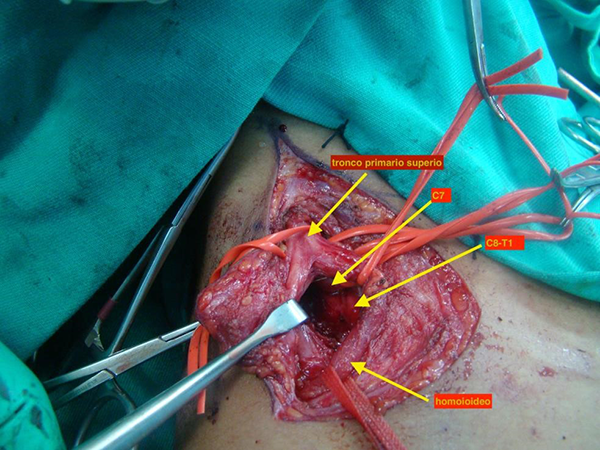

Se realiza abordaje del plexo braquial supra clavicular (foto 3) en el que se identifica tumoración ósea que comprime las raíces inferiores del plexo braquial a nivel supraclavicular.

Se realiza radioscopia para identificar trayecto de difícil interpretación por el tipo de tejido cartilaginoso (foto 4) y resección ósea y neurolisis de las raíces del plexo braquial (foto 5).

Foto 5. Exostosis cervical que comprime las raíces inferiores C8 y T1

Foto 6. Tras exéresis de exostosis cervical, neurólisis de las raíces de plexo